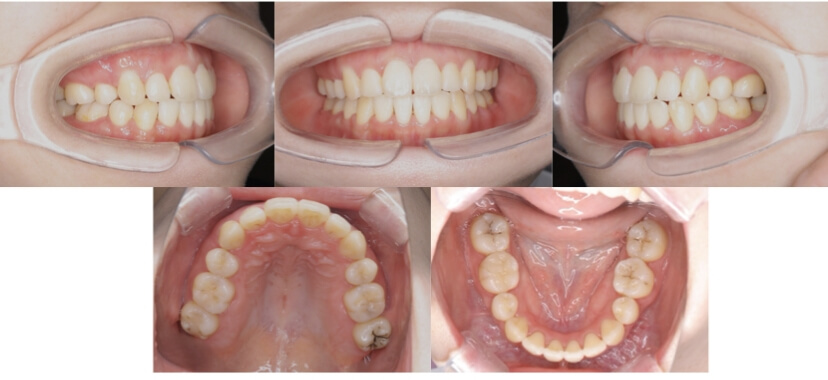

BEFORE

AFTER

症例3

叢生

抜歯

ブラケット矯正

上下顎叢生(上下の前歯のガタガタ)のケースです。

装置はラビアル(上下表側)で、上下顎の小臼歯を4本抜歯を行っています。抜歯したスペースを使って、上下の前歯の後方移動と叢生(ガタガタ)の改善を行っています。

主訴 八重歯を治したい。

年齢・性別 25歳 女性

お住まいの地域 神奈川県川崎市

治療方針 抜歯スペースを利用して上前歯の叢生(ガタガタ)の改善

抜歯部位 上下顎左右第一小臼歯

使用装置 ラビアル(上下表側)、顎間ゴム

治療期間 1年11か月

治療回数 16回

リテーナー クリアリテーナー